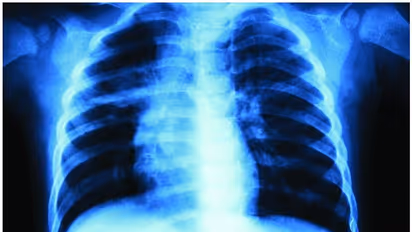

അമ്പലപ്പുഴ: വാഹനാപകടത്തിൽ പരിക്കേറ്റ് ആലപ്പുഴ മെഡിക്കൽ കോളജ് ആശുപത്രിയിലെത്തിച്ച യുവാവിന്റെ ഇടത് നെഞ്ചിന് പകരം വലതു നെഞ്ചിന്റെ എക്സ്റേ എടുത്തതായി പരാതി. പായൽക്കുളങ്ങരയിൽ വെച്ച് ബൈക്കിൽ കാറിടിച്ചാണ് യുവാവിന് പരിക്കേറ്റത്. നെഞ്ചിനും കാലിനും പരിക്കേറ്റ യുവാവിനെ നാട്ടുകാർ മെഡിക്കൽ കോളജ് ആശുപത്രിയിലെത്തിച്ചു. ഇടത് നെഞ്ചിൽ വേദനയുണ്ടെന്ന് അറിയിച്ചതിനെത്തുടർന്നാണ് ഡോക്ടർ എക്സ്റേ എടുക്കാൻ നിർദേശിച്ചത്. എന്നാൽ, എക്സ്റേ എടുത്തത് വലതു നെഞ്ചിന്റേതായിരുന്നു. പരിശോധനയിൽ കുഴപ്പമൊന്നുമില്ലെന്ന് ഡോക്ടർ അറിയിക്കുകയും ചെയ്തു.

വേദന അസഹനീയമായതിനെത്തുടർന്ന് യുവാവിനെ തിരുവല്ലയിലെ സ്വകാര്യ ആശുപത്രിയിലേക്ക് മാറ്റി. ഇവിടെ നടത്തിയ പരിശോധനയിലാണ് എക്സ്റേ മാറിയ വിവരം തിരിച്ചറിഞ്ഞതും ഇടത് നെഞ്ചിൽ നീർക്കെട്ടുള്ളതായി കണ്ടെത്തിയതും. കാലിന് ഗുരുതരമായി പരിക്കേറ്റ യുവാവിനെ പിന്നീട് അടിയന്തിര ശസ്ത്രക്രിയയ്ക്ക് വിധേയനാക്കി.